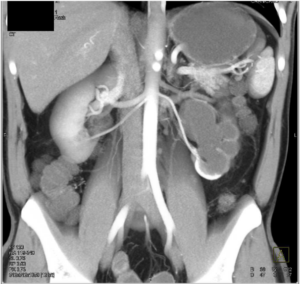

Chụp CT và MRI hệ niệu là phương pháp được lựa chọn, tùy trường hợp và trang thiết bị kỹ thuật, tiếp theo sau siêu âm trong hội chứng khúc nối bể thận – niệu quản cũng như trong bệnh lý tắc nghẽn hệ niệu. Chụp uroscan giúp khảo sát tốt hình thái hệ thận – niệu và đánh giá định tính chức năng thận . Chụp uroMRI ngoài khảo sát hình thái còn đánh giá định lượng chức năng bài tiết của thận.